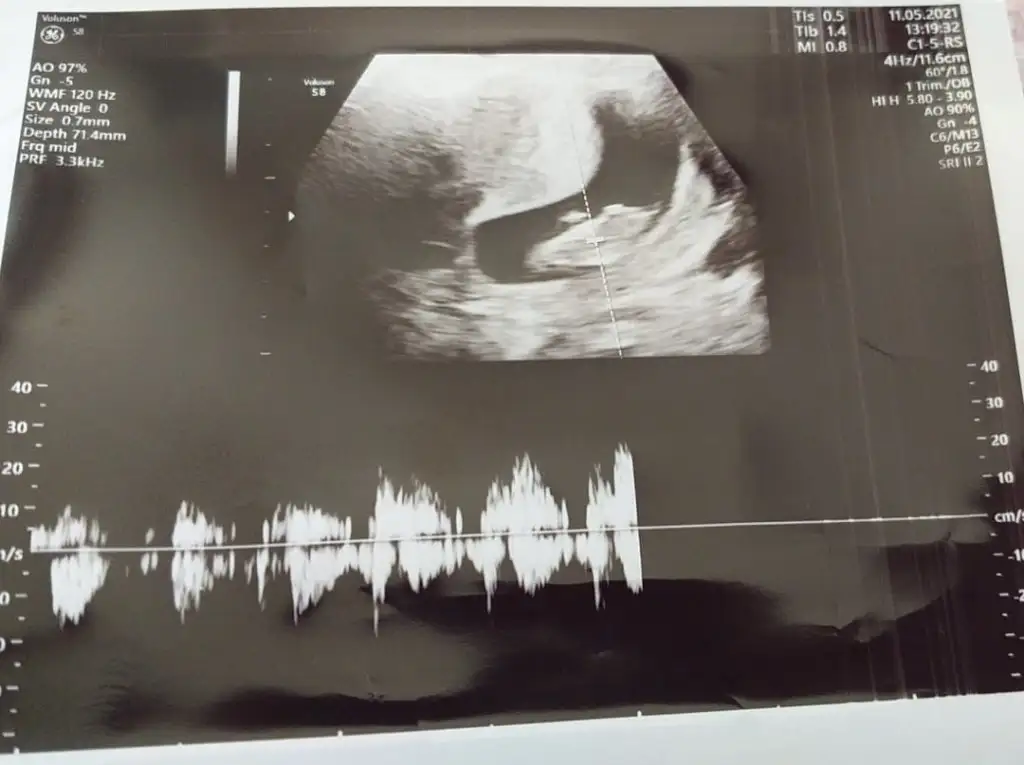

Merhaba arkadaşımın karından ultrason resmi cinsiyet tahmini yapar mısınız ?

Resim görünüyordur umarım

Bu sırttan çekilmiş sanki. Yandan olması lazım.

Bilemiyorum ki 2 tane göndermişti bana bir tanesi bu kadar belli değildi o yüzden bunu yükledim diğer resmi ekledim şimdi